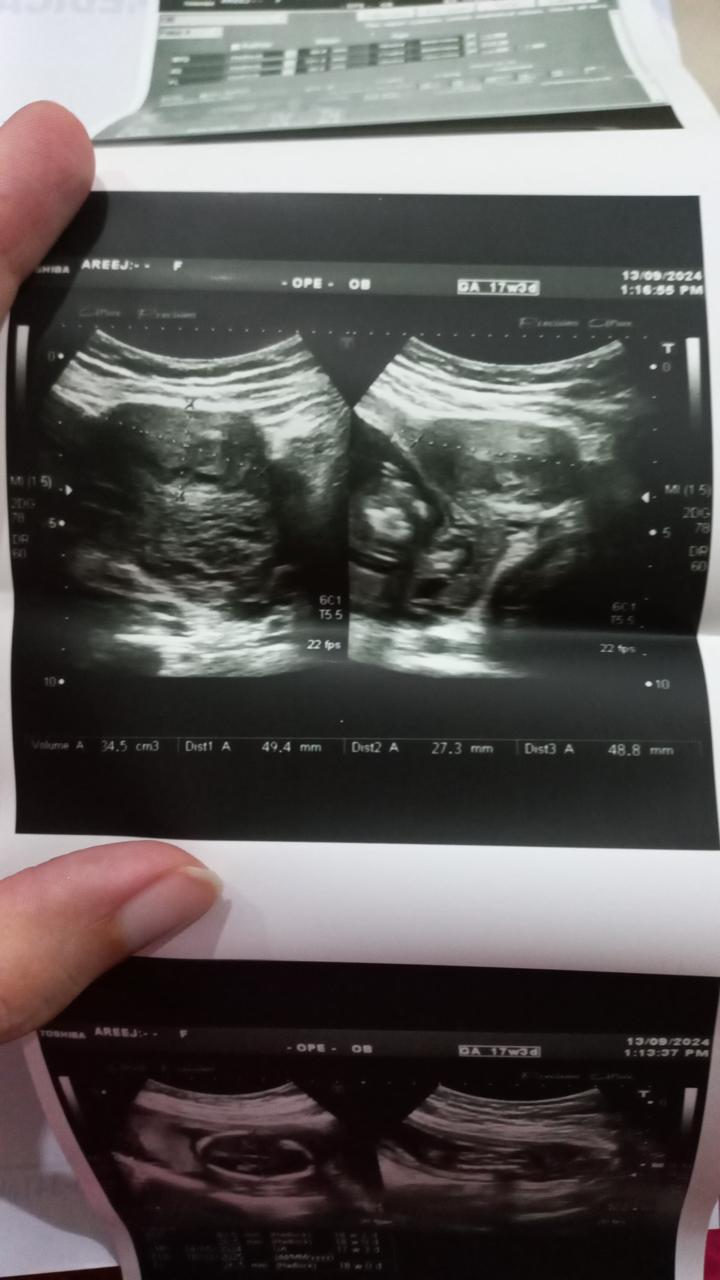

Doctor hope you are doing well. My wife is pregnant of 20 weeks 4 days now and her anomaly scan was done at around 18 weeks. According to reports the baby had lateral ventricle size 6mm other ventricles like left and right was normal. The doctor said come again after 21 week we will do your anomaly scan again. We are so worried and tense even not sleep well every day. I’ll attach the report. Can you please tell me is everything okay and could you please explain little bit. Thanks in advance,

Attach Photo here: